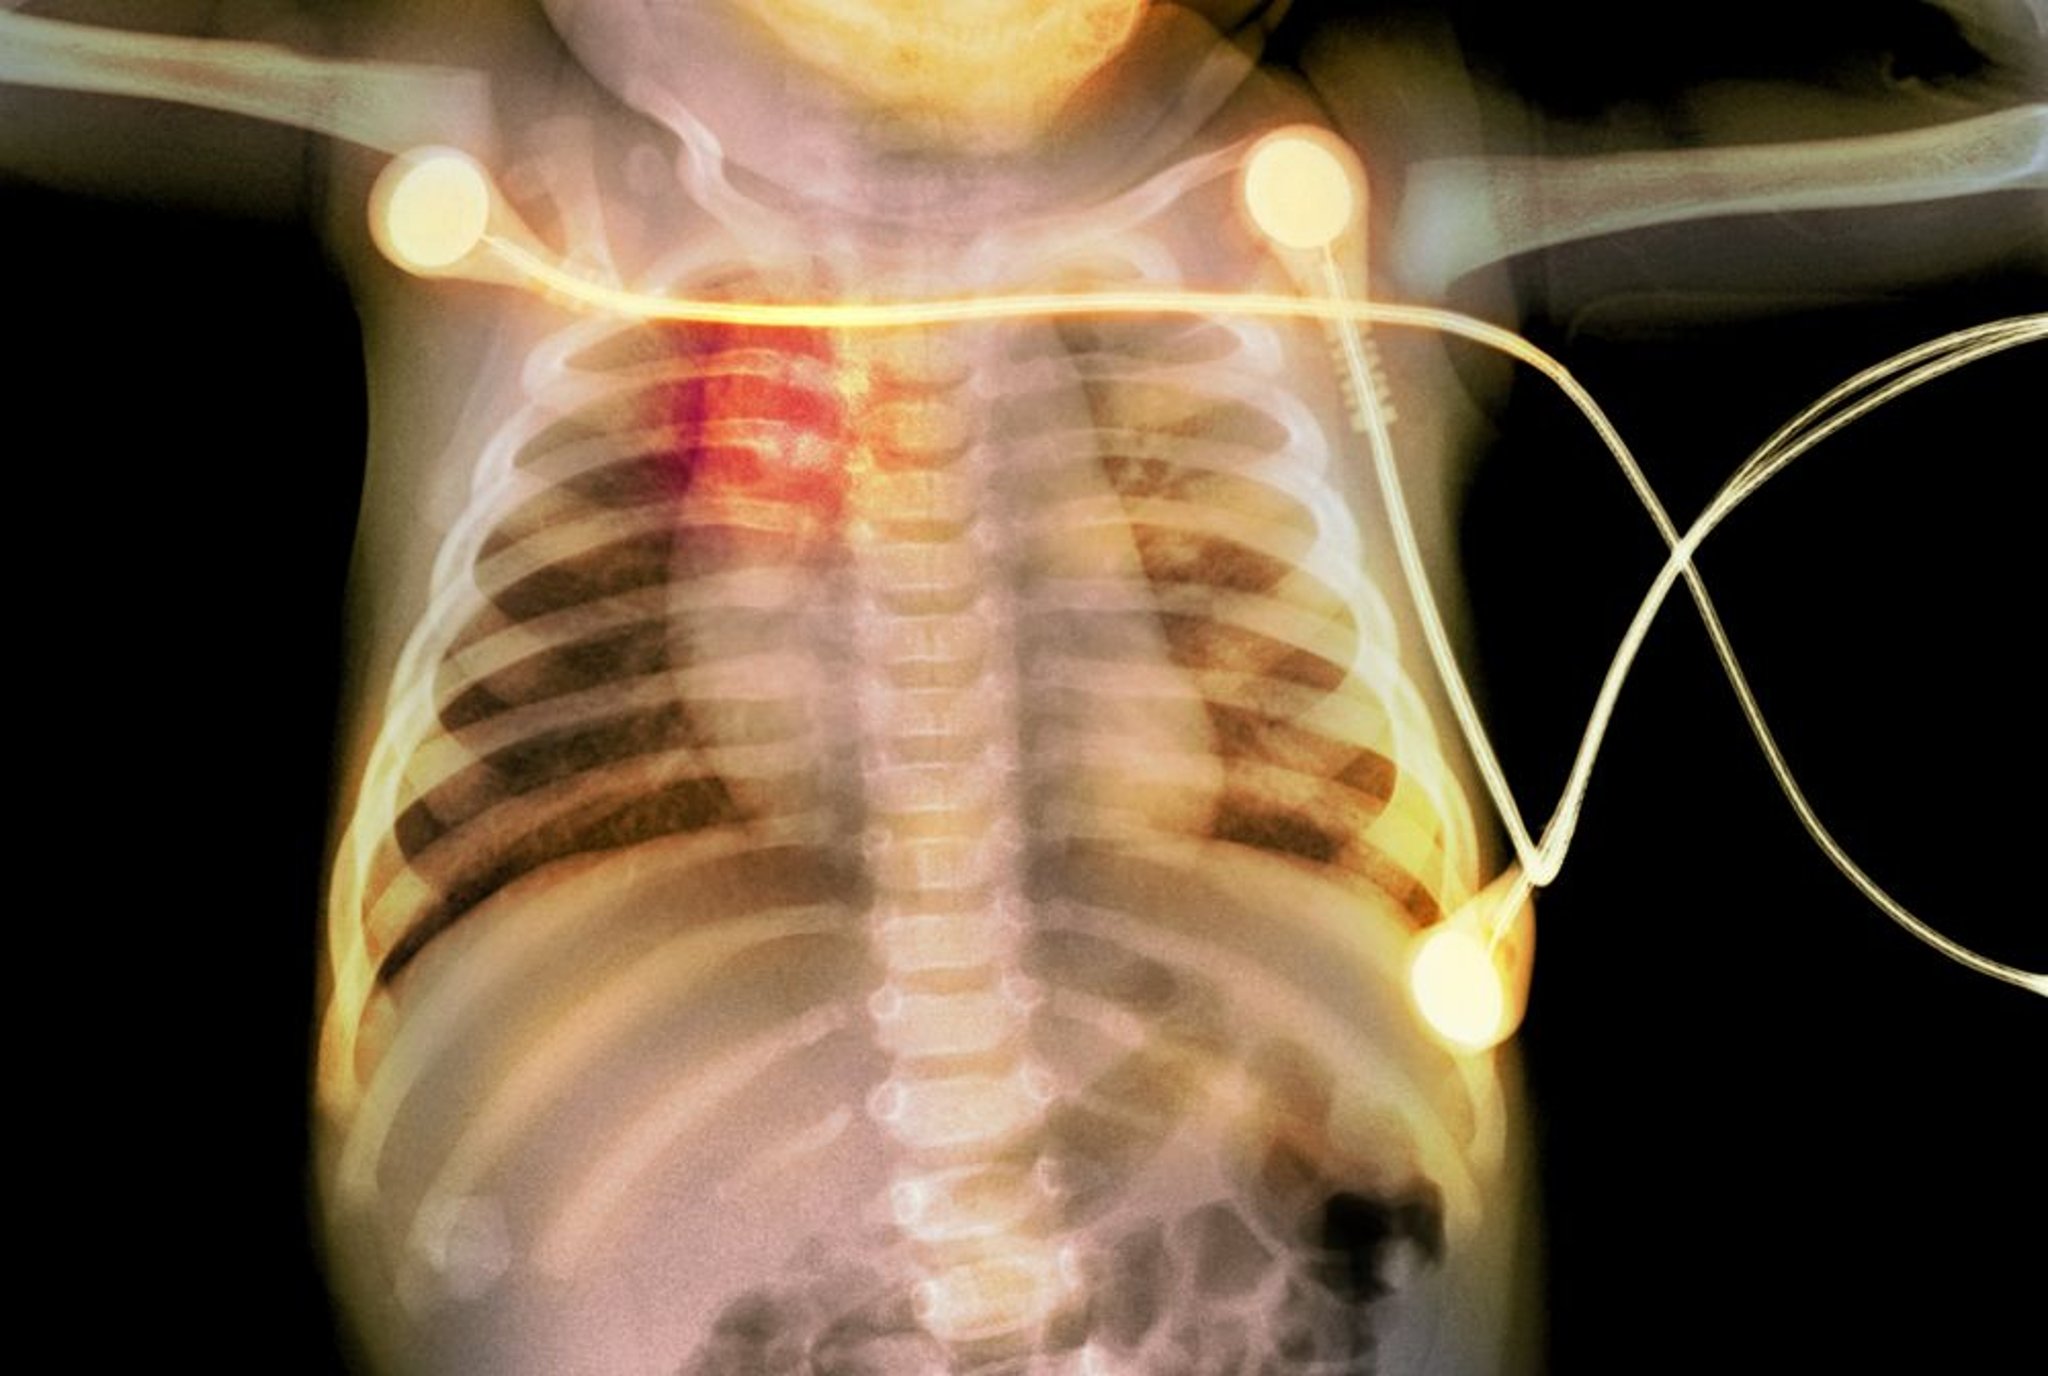

乳児における肋骨骨折

このX線写真には,乳児の肋骨骨折(赤で強調)が認められ,小児虐待が示唆される。